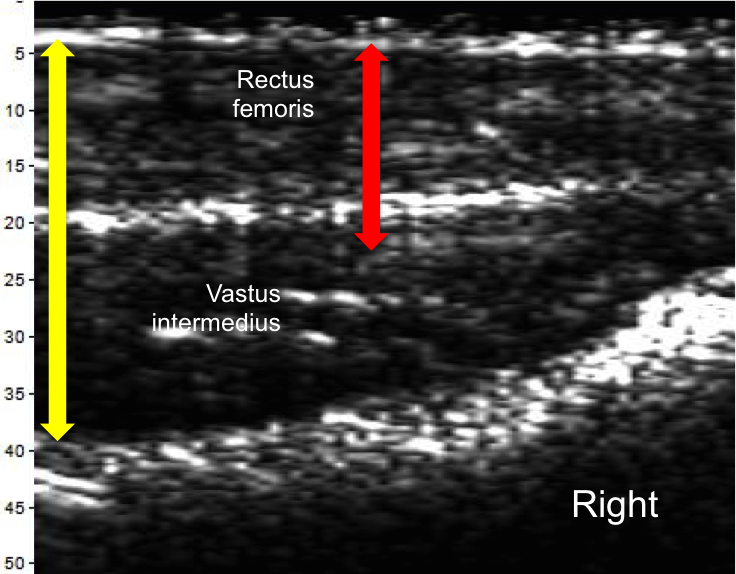

Muscle Imbalance

The scans below taken of the left and right quadricep from the midpoint to near the patella were recorded on the same day. The scans show clear differences. The yellow and red arrows represent the same thickness in each image, showing significant imbalance. The ratio of the Rectus Femoris thickness to the Vastus intermedius is 1.3 for the left leg and 0.8 for the right leg.